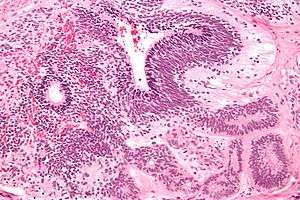

| Micrograph of the primitive neuroepithelium of an immature teratoma. H&E stain. | |

Like a mature teratoma, it contains several different types of tissue such as hair, muscle, and bone. Unlike a mature teratoma, it contains primitive neuroepithelium.